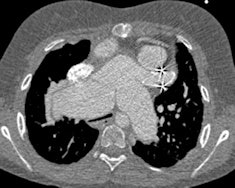

MDCT using a low radiation dose protocol is the best diagnostic tool for assessing the central airway, cardiovascular and mediastinal abnormalities, and the lung parenchyma in children, and the relevant information can be acquired with a single-volumetric data set acquisition, she stated. Using thin-slice collimation acquisition with inherent isotropic resolution, the image data can be manipulated and reformatted to display 2D and 3D images with the same spatial resolution as the axial images, thus enhancing diagnostic accuracy and providing data that can be used in presurgical planning and patient management.

Furthermore, wider coverage with faster tube rotation speeds has reduced overall imaging time, leading to a decrease in sedation needs, improved image quality due to reduction in motion and respiratory artifacts, and high-quality depiction of small vessels due to improved contrast enhancement as a result of higher contrast concentration over a shorter time period.